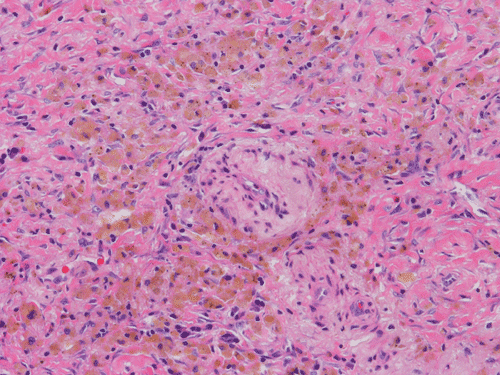

At scanning magnification (Panel A), the lung parenchyma is replaced by some coalescing fibrous nodules. The degree of involvement is variable at different fragments (Panel B and C). In the less affected areas, there are some fibrotic thickening of the septa (Panel C). In some areas, the changes are minimal and the pleural appear to be uninvolved (Panel D and E). In low to medium magnifications, these nodules of fibrosis contains a large number of hemosiderin laden macrophages (Panel F and G) admixed with fibrous tissue. The diagnostic tissue, however, is present in areas with increased cellularity. In these areas, there is a background of cells with a moderate amount of cytoplasm and bland nuclei. Some of these nuclei have kidney shape (arrow in Panel H). In some areas, many of the nuclei have a deep nuclear groove that resemble a coffee bean (arrow in Panel I). In the third type of areas, the nuclear grooving is not distinct (Panel J). Prominent eosinophilic infiltrations are almost always present. Immunohistochemistry on CD1a revealed many positive cells (Panel L). Also present in the specimen are multiple small blood vessels with thickened intima (Panel K). A Movat pentachrome stain demonstrates an internal elastic layer in these vessels and confirms that these are arteries (Panel M and N).

Pathologically, PLCH can be broadly divided into an early or cellular stage and a late or fibrotic stage. Demonstration of LCs is of critical importance for a correct diagnosis. The morphology of LCs is similar to LCH in other organs. LCs are characterized by a deep nuclear groove which lead to “coffee bean-shaped” or “kidney-shaped” nuclei. In most cases, the level of atypia and pleomorphism is low. A moderate amount of amphophilic to weakly eosinophilic cytoplasm is present. The cytoplasmic membrane is indistinct. Eosinophils and chronic inflammatory cells, varying from scant to abundant, are present. Except for a scant frankly pleomorphic cases, the level of pleomorphism and atypia is minimal to low. Eosinophilic abscesses with central necrosis may be present. Immunohistochemically, LCs are similar to their normal counter parts and are positive for CD1a and S100. At the ultrastructural level, Birbeck granules can be demonstrated. For most cases, the diagnosis can be established by histopathologic criteria but these additional features help to confirm the diagnosis.

In the end stage, the exhausted lesions are predominantly fibrotic and largely depleted of LCs. In some regions, the fibrosis may surround cystic spaces of variable diameter to form large areas of honeycombing. This is especially predominant in the upper lobes. In cases where parenchymal scaring is present, the pulmonary function will be largely compromised. At this stage, both pulmonary function tests and radiologic findings may suggest diffuse lung disease, but biopsy will show stellate fibrotic lesions centered on the terminal airways with no identifiable interstitial inflammation. Pulmonary vasculopathy (in areas of lung remote from parenchymal nodules) is also seen in late stage PLCH. Vasculopathy manifests as intimal fibrosis, medial hypertrophy or luminal obliteration involving both venules and arteries. This may account for pulmonary hypertension seen late in PLCH.